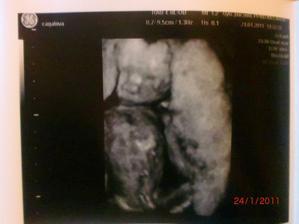

24.1.2011 - dozvěděli jsme se,že čekáme druhýho chlapečka - Matyáška

4.2.2011 - Velký utz,potvrzen chlapeček,vše je v pořádku,jen je Matýsek moc dole a tak byl problém ho změřit..